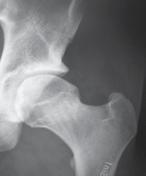

a. Vad är en s k CAM-lesion? (1p)

b. Vilka symtom kan en patient ha med en sådan lesion? (1p)

c. Vilka är de röntgenologiska undersökningsfynden? (1p)

a. CAM-lesion kan vara en orsak till femuroacetabulär impingement (FAI) där man har en påbyggnad på collum femoris främre övre omfång.

b. Symtom kan vara höftsmärta och inskränkt rörlighet, ssk flexion men även inåtrotation och adduktion.

c. På slätröntgen eller CT, alternativt MR ses ”Pistol-grepps-deformitet”, benpåbyggnad vid övergång superiort mellan caput-collum och förlust av sfäriciteten av caput femoris.